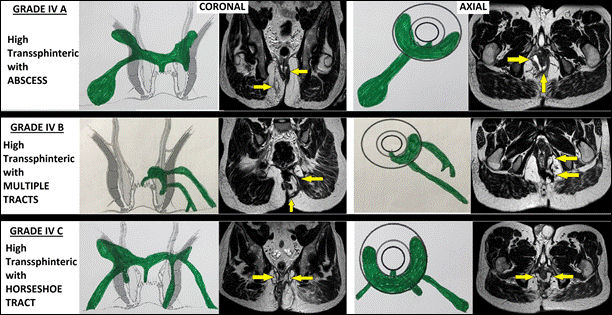

IV |

Rò xuyên cơ thắt ngoài mức cao (>1/3) mang tính phức tạp, gồm: IV-A:Có áp-xe IV-B:Có nhiều đường rò IV-C:Rò dạng móng ngựa |